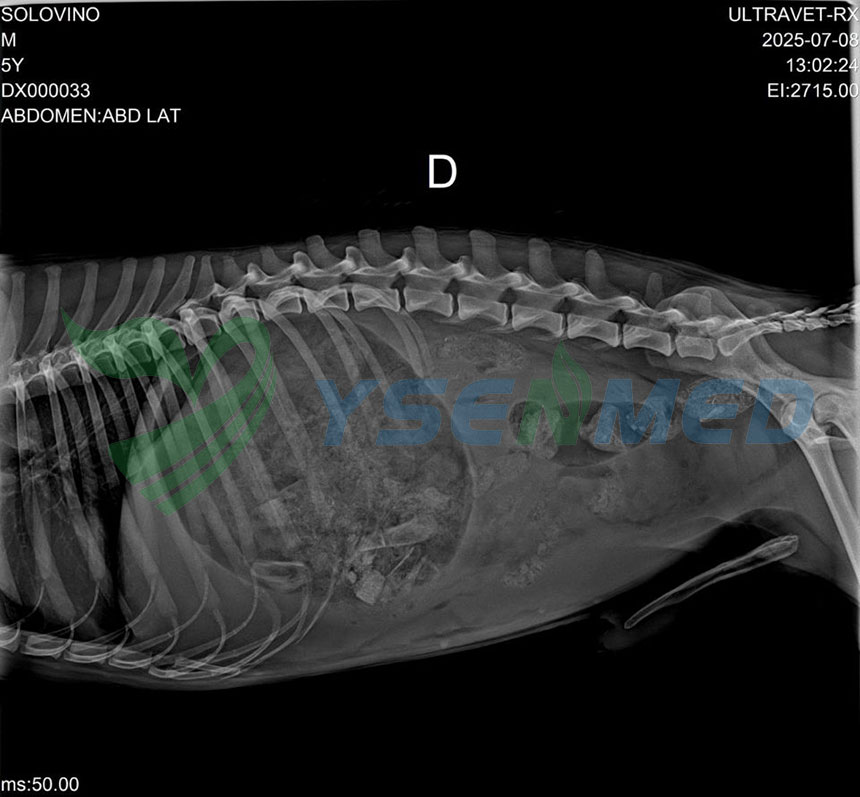

YSENMED installed a YSX056-PE 5.6kW X-ray for Mr. Milton in Ecuador. He shared some installation photos and confirmed it works, giving a real boost to local veterinary imaging and our growing partnership. Thank you Mr. Milton!